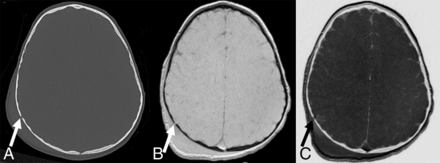

Our study evaluated the diagnostic accuracy of black bone MR imaging in detecting skull fractures in children with head trauma compared with CT. The black bone MR imaging sequence showed a sensitivity of 66.7% and a specificity of 87.5% in the detection of skull fractures (Fig 1). The specificity is acceptable, while the sensitivity is low. To determine the reasons for the low sensitivity of the black bone MR imaging sequence, we studied the 4 false-negative linear fractures and the 2 false-positive linear fractures. In 2 children younger than 2 years of age, false-negative linear fractures were misinterpreted as cranial sutures (2 false-negative cases). Furthermore, the 2 false-positive cases were children in the younger age group (younger than 2 years), with cranial sutures being falsely identified as linear fractures. In young children, the presence of open sutures is known to increase the diagnostic uncertainty of skull fractures on 2D images as recently shown by a head CT study.14 In head CT studies, the addition of 3D reconstructions to the 2D dataset has been shown to increase the reader's confidence for correct differentiation of sutures and other nonfracture-related linear lucencies such as vascular channels versus linear fractures.14 The addition of 3D reconstruction to the 2D black bone MR images as shown for the study of craniosynostosis9 could potentially decrease the misinterpretation as shown for head CT.

A, Axial CT image shows a nondisplaced linear fracture of the right parietal bone (arrow) with extracranial soft-tissue swelling. Black bone (B) and inverted black bone (C) MR images reveal equivalent visualization of the right parietal fracture (arrows), as well as overlying soft-tissue swelling.